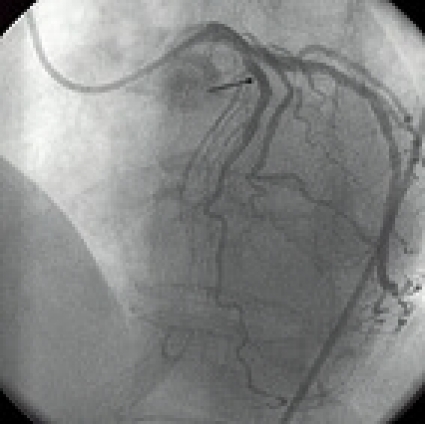

I jämförelsen mellan PCI och trombolys vid hjärtinfarkt med ST-förhöjning kan man ställa sig frågan varför PCI inte i större utsträckning påverkar mortaliteten, då metoden återskapar ett bra flöde (TIMI 3) i kranskärlet i 70–90 procent av fallen [12-14] och den bästa trombolysregimen i 50 procent [17]. Om man extrapolerar resultaten från den angiografiska substudien i GUSTO I [17] borde ett bra flöde i det infarktrelaterade kranskärlet resultera i en mortalitet på ca 5 procent, vilket antyder att det finns utvecklingsmöjligheter för PCI-tekniken.